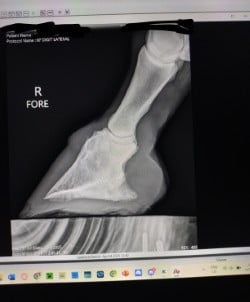

Rennie, a 2016 AQH, is a medical mystery; by all means, he shouldn't be standing, running, or jumping around the paddock. He was rescued in 2023 by a small family who help horses, skin and bones with a severe and constant limp in his right foreleg. We got him in February 2024, a great weight, but he still had a mysterious lameness that we couldn't figure out. After research, I found scoot boots. They took him from constant 3-4/5 lameness to a 1-2 lameness. Sound to be ridden (although he is just a paddock pet) We took x-ray at Texas A&M, the whole team was shocked, wondering how he is still alive with full fusion of his coffin, navicular and P3. His not only walking, but he is sound, happy, and a loving liberty pony. He came from a background of severe abuse. He has the physical and emotional scars of control-based training methods that left deep trauma: rope burns, whip marks, slashed legs, and twisted ears told a story of cruelty I wouldn’t wish on any animal. He had spent his final months before rescue in the auction pipeline.

I turned back to Rennie’s old farrier, the only one he and I trusted, but his flare-ups worsened, and without clear x-rays, we had little understanding of what was truly happening inside his hoof. I consulted my vet about quality of life, corrective shoeing, and every option we had left. When Texas A&M provided new x-rays, the truth was undeniable. His fusion was so severe that most professionals believed there was no choice but euthanasia. One corrective shoer refused to even see him, stating simply, "The horse should be put down."

But the team at Texas A&M saw what I saw—Rennie was defying the odds. Corrective shoeing wasn’t the answer. Traditional shoes would only add more stress, but Scoot Boots gave him freedom. They allowed his hoof to move as naturally as possible, relieving pressure without restricting movement. The specialists were amazed—not just at his ability to move, but at how much the boots had helped him. Without them, he wouldn’t be sound. Without them, I would have had to make the hardest decision.